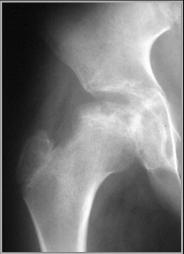

Legg-Calve-Perthe’s Disease